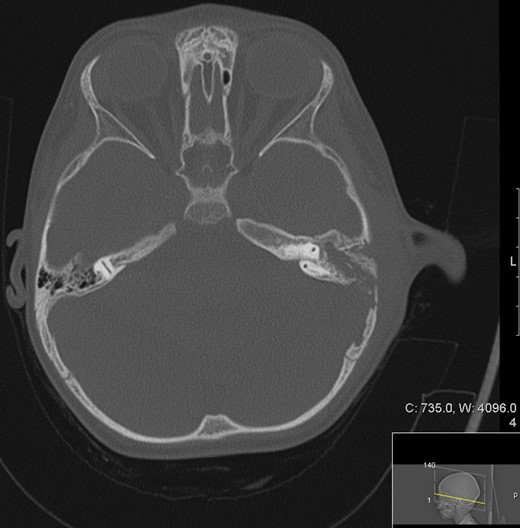

Patient underwent MRI imaging (Day 6 post drainage) which showed near resolution of the epidural and extracranial collection (Fig. 3). Upon review of images it was decided that no further surgical input was necessary, and the patient was discharged with follow up planned within 2 weeks.

Transverse magnetic resonance image 3 months post op showing some residual inflammation within the post-surgical mastoid cavity (white asterisk) and resolution of collection.